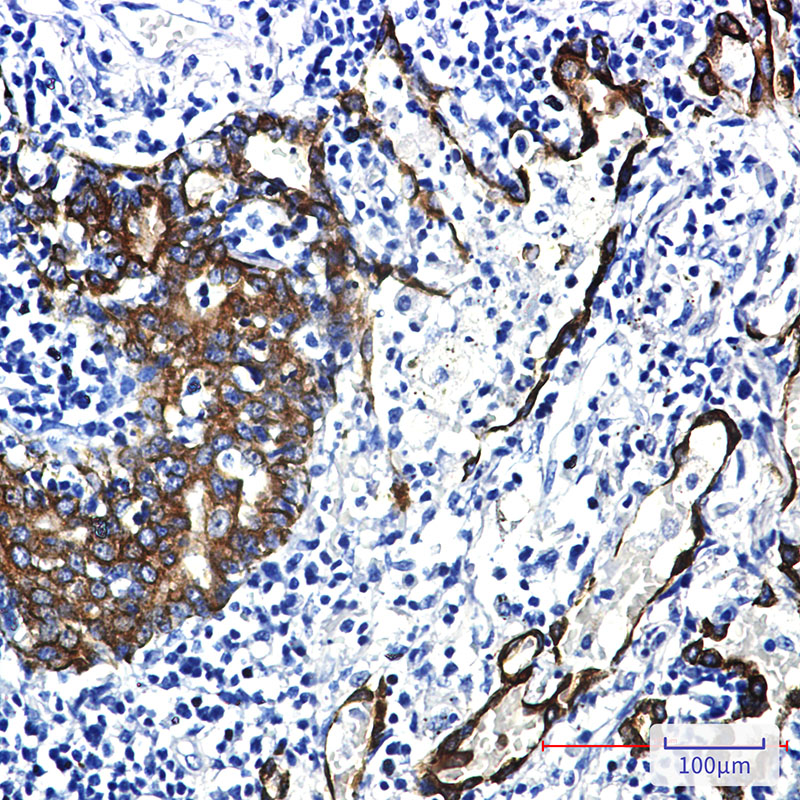

IHC 1/50-1/100 Human,Mouse,Rat

Cytokeratin 7 (CK7) is a member of the cytokeratin family of intermediate filament proteins, which are essential structural components of epithelial cells. These proteins are classified into acidic Type I and basic Type II keratins, forming heteropolymers to maintain cellular integrity. CK7. a Type II keratin with a molecular weight of approximately 54 kDa, is expressed in specific epithelial tissues, including glandular and ductal epithelia of the respiratory, biliary, urinary tract, and endometrium.

In diagnostic pathology, CK7 antibodies are widely used in immunohistochemistry (IHC) to identify epithelial origin and differentiate between carcinomas. For instance, CK7 positivity is common in adenocarcinomas of the lung, breast, and ovary, while it is typically absent in colorectal, prostate, and hepatocellular carcinomas. This marker is often paired with CK20 to refine tumor classification (e.g., CK7+/CK20– in lung adenocarcinoma vs. CK7–/CK20+ in colorectal carcinoma).

CK7 antibodies also aid in detecting metastatic tumors of unknown primary origin by highlighting tissue-specific expression patterns. However, interpretation requires caution, as staining intensity and distribution may vary due to technical factors or tumor heterogeneity. Clinically, CK7 remains a cornerstone in differential diagnosis, though results should always correlate with clinical context and additional biomarkers.